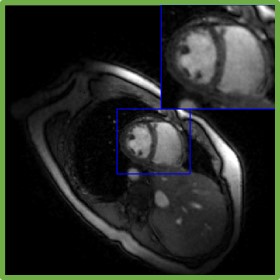

In Fig. 7, we compare the region of interest for SToRM500, SToRM with 150 frames (SToRM150), the proposed method with two different d𝑑d values, the unsupervised Time-DIP approach, and the low-rank algorithm. From Fig. 7, we observe that the proposed scheme can significantly reduce errors in comparison to SToRM150. Additionally, the proposed scheme is able to capture the motion patterns better than Time-DIP, while the low-rank method is unable to capture the motion patterns. From the time profile in Fig. 7, we notice that the proposed scheme is capable of recovering the abrupt change in blood-pool contrast between diastole and systole. This is due to inflow effects associated with gradient echo (GRE) acquisitions. In particular, the blood from regions outside the slice enters the heart, which did not experience any of the former slice-selective excitation pulses; the differences in magnetization of the blood with no magnetization history, and that was within the slice, results in the abrupt change in intensity. We note that some of the competing methods such as Time-DIP and low-rank, blur these details.

Refer to caption

(a) Visual comparisons

(b) Time profiles

Figure 7: Comparisons with the state-of-the-art methods. The first column of (a) corresponds to the reconstructions from 500 frames (similar-to\sim 25s of acquisition time), while the rest of the columns are recovered from 150 frames (similar-to\sim 7.5s of acquisition time). The top row of (a) corresponds to the diastole phase, while the third row is the diastole phase. The second row of (a) is an intermediate one. Fig. (b) corresponds to the time profiles of the reconstructions. We observe that the proposed (d=40𝑑40d=40) reconstructions exhibit less blurring and fewer artifacts when compared to SToRM150 and competing methods.